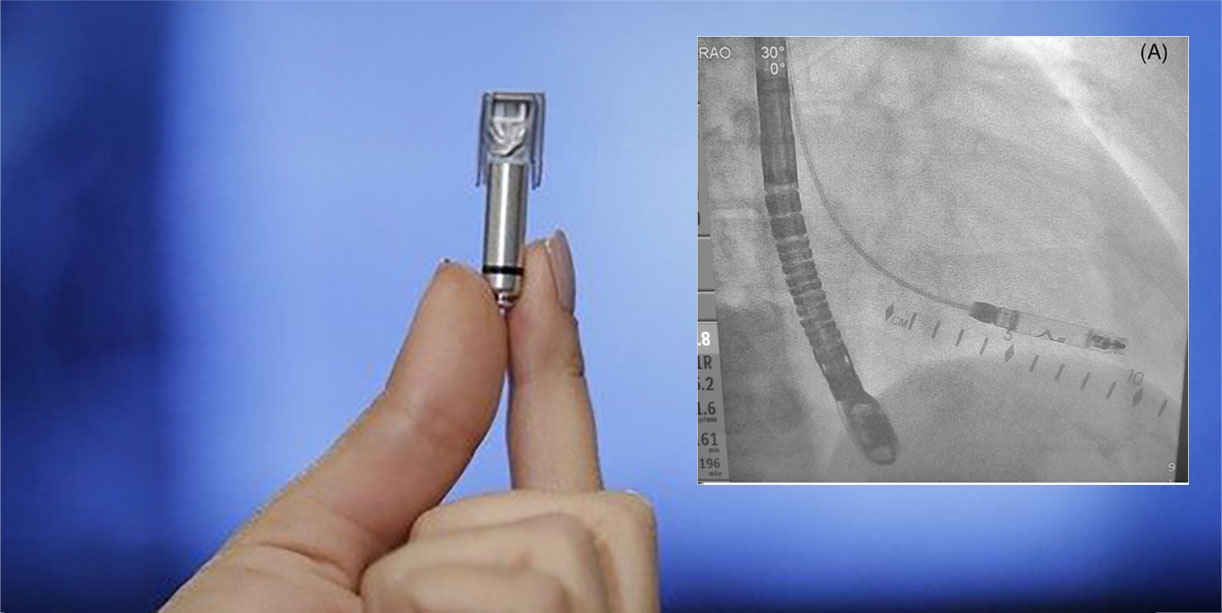

Çift odacıklı kurşunsuz kalp pilleri, kalbin üst (atriyal) ve alt (ventriküler) odacıklarını uyararak ritmi düzenler. Hastanın aktif spor yaşamına devam etmek istemesi nedeniyle bu yöntem uygun bir seçenek olarak sunuldu. Yeni nesil AVEIR cihazı, sağ iç jugular ven yoluyla minimal invaziv bir işlemle yerleştirildi. Geleneksel femoral ven yerine bu yöntemin seçilmesi, hastanın daha hızlı toparlanmasını sağladı.

Yerleştirme işlemi sırasında veya sonrasında herhangi bir komplikasyon görülmedi. Üç ay sonra hasta spor yapmaya ve normal aktivitelerine dönebildi. AVEIR cihazı, geleneksel kalp pillerine göre 10 kat daha küçük ve kablosuz tasarımı sayesinde kalp tarafından emiliyor. Dr. Cortez, bu yöntemin çocuklar dahil herkes için yeni bir standart oluşturduğunu belirterek şu yorumu yaptı: “Artık hiçbir kısıtlama olmadan kurşunsuz kalp pili avantajlarından faydalanabilirler.”

UC Davis’te görev yapan Dr. Dan Cortez, 13 yaşındaki bir çocuğa dünyada ilk kez çift odacıklı kurşunsuz kalp pili implantasyonu gerçekleştirerek tıp dünyasında bir ilke imza attı. Doğuştan tam kalp bloğu olan ve düşük nabız nedeniyle baygınlık hissi yaşayan hasta, minimal invaziv bir yöntemle tedavi edildi. Sağ iç jugular ven yoluyla yerleştirilen AVEIR cihazı, geleneksel kalp pillerinden farklı olarak kablo içermiyor ve kalp tarafından emilebiliyor. Bu cihaz, spor gibi fiziksel aktivitelerde kısıtlama olmaksızın hastanın hayat kalitesini artırmayı hedefliyor.

İşlem sonrası herhangi bir komplikasyon yaşanmayan hasta, üç ay içinde normal aktivitelerine döndü. Daha önce yalnızca yetişkinlerde kullanılan bu yeni nesil cihaz, çocuklarda da güvenle uygulanabileceğini kanıtladı. Kalp ritmini hem atriyal hem de ventriküler düzeyde düzenleyen cihaz, gelecekte kurşunsuz kalp pillerinin çocuklarda yaygınlaşabileceğini gösteriyor. Bu başarı, çocuk kalp sağlığı alanında yeni tedavi yöntemlerinin geliştirilmesine ışık tutuyor.